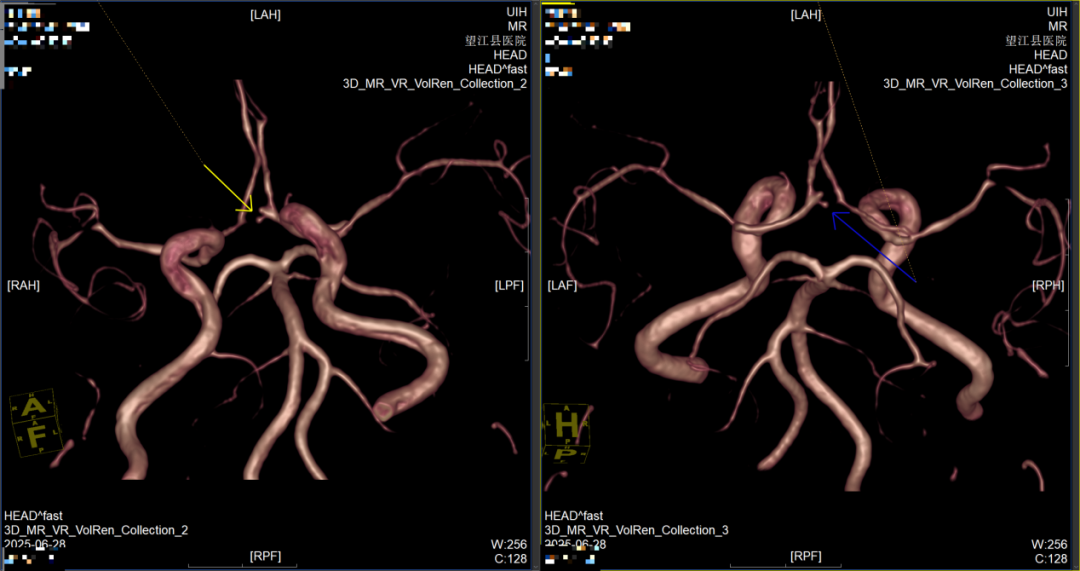

1.MRA(磁共振血管成像):揪出腦內(nèi)“隱形炸彈”——小動脈瘤;顱內(nèi)動脈瘤破裂是導(dǎo)致猝死性蛛網(wǎng)膜下腔出血的首要原因,而多數(shù)患者在破裂前毫無癥狀。傳統(tǒng)檢查容易漏診<3mm的小動脈瘤,但MRA無需注射造影劑即可清晰顯示血管三維結(jié)構(gòu),靈敏度高達(dá)95%,能精準(zhǔn)識別微小動脈瘤的位置、形態(tài)和血流動力學(xué)特征,為后續(xù)干預(yù)提供關(guān)鍵依據(jù)。

前交通動脈瘤